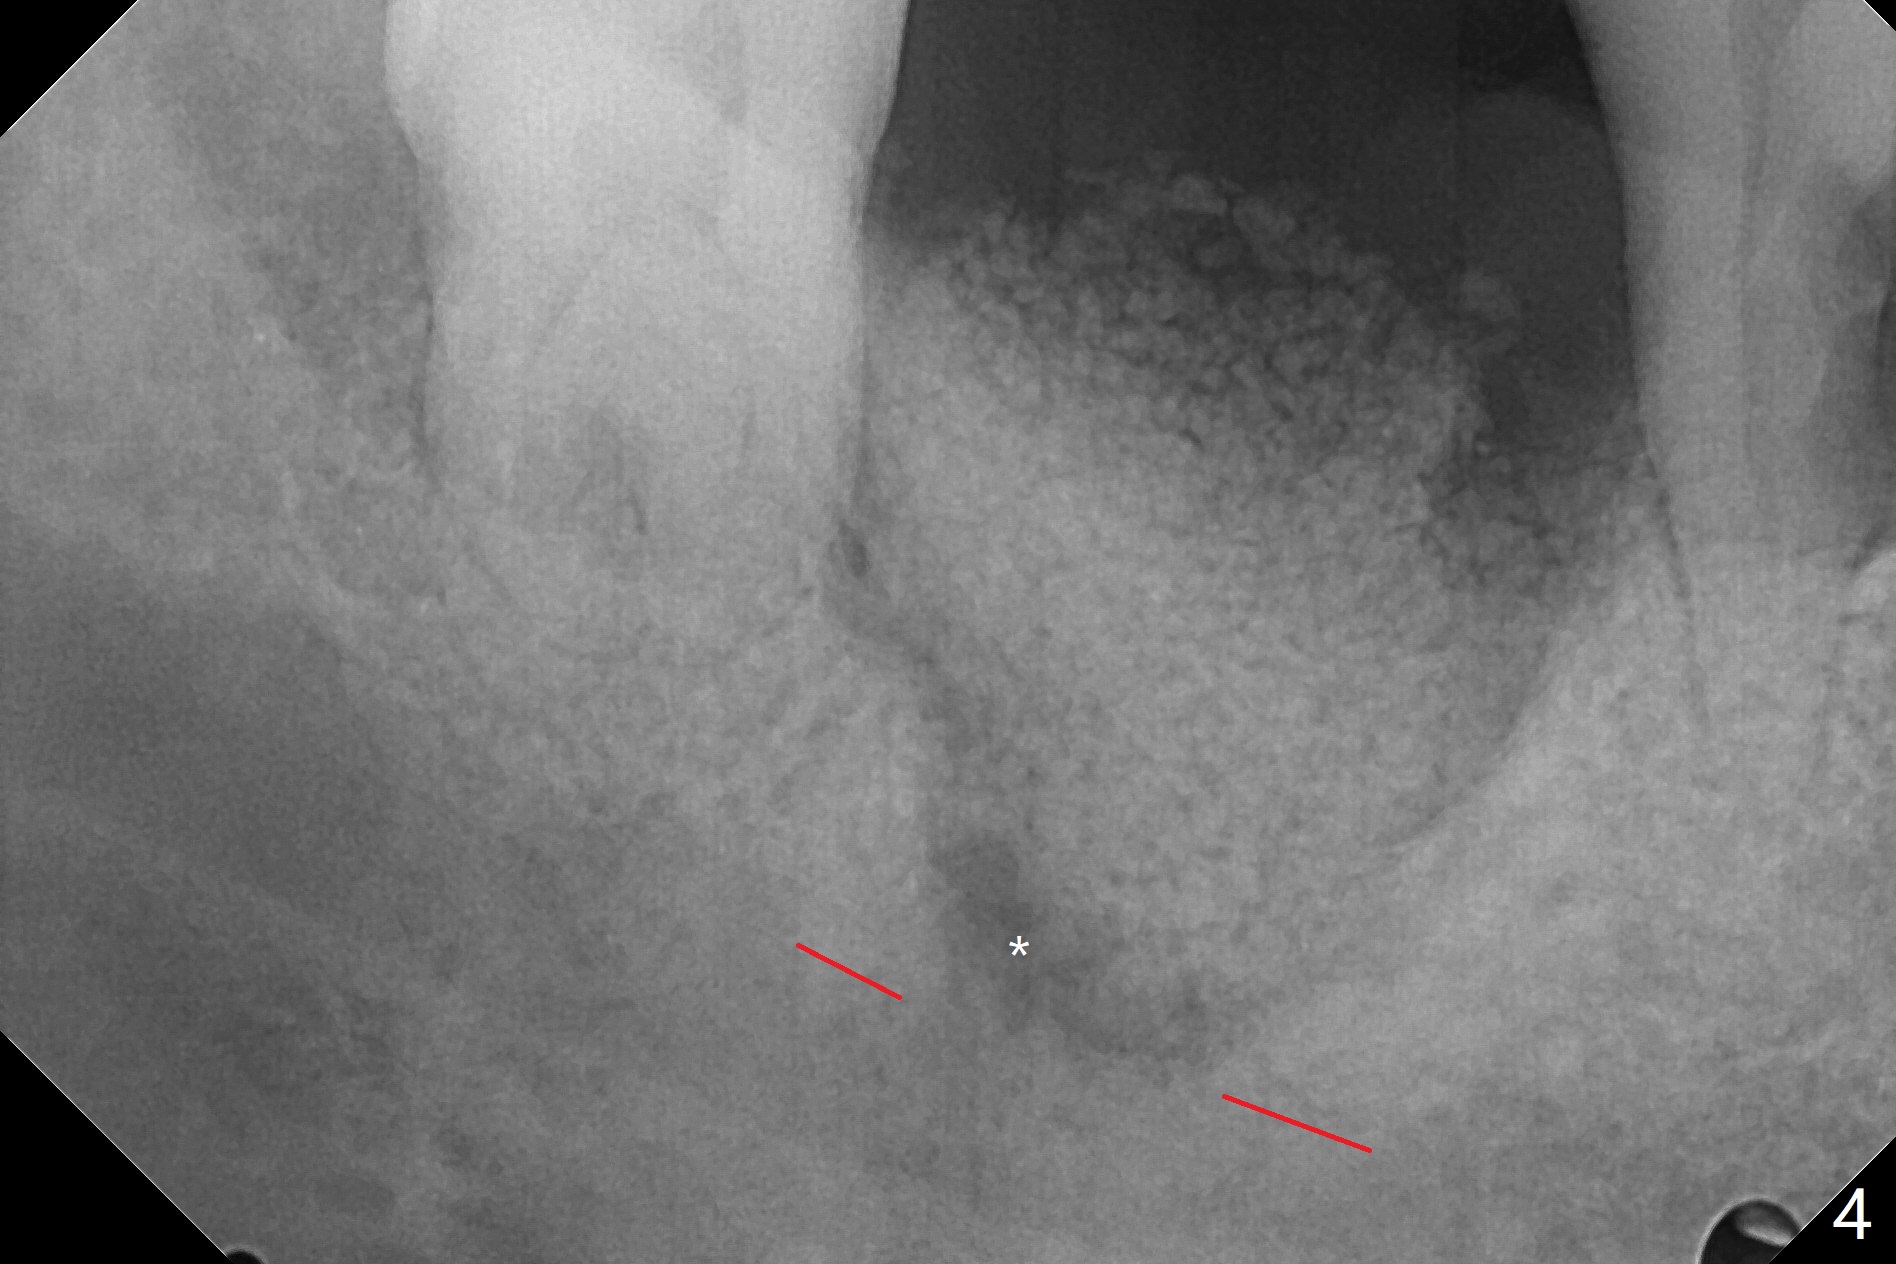

40岁男,牙周炎(图一,4年前拍摄),现在要求拔除31号牙,劝导后同意植骨,问题在于牙根长(图二),可能接近神经(红虚线)。拔牙后,舌侧骨板缺失,不敢大胆在根尖清创,术中拍摄根尖片(图三),牙槽窝根尖接近神经管,最后可能遗留些根尖肉芽组织(图四:*(最好拍摄CT))。粘性骨粉表面覆盖PRF和Cytoplast,使用4-0 PTFE缝线,没有使用牙周敷料,因为后者往往与缝隙粘连,脱落时缝线必须撤除,可能影响不可吸收膜固定。不过这次不可吸收膜术后四天脱落,术后五天骨粉好像丢失不多(图五),可能与粘性骨粉有关。下次需要牙周敷料,牙齿长,敷料固定好。Return to Protect Graft 19 位点保存 Xin Wei, DDS, PhD, MS 1st edition 06/28/2021, last revision 07/09/2021